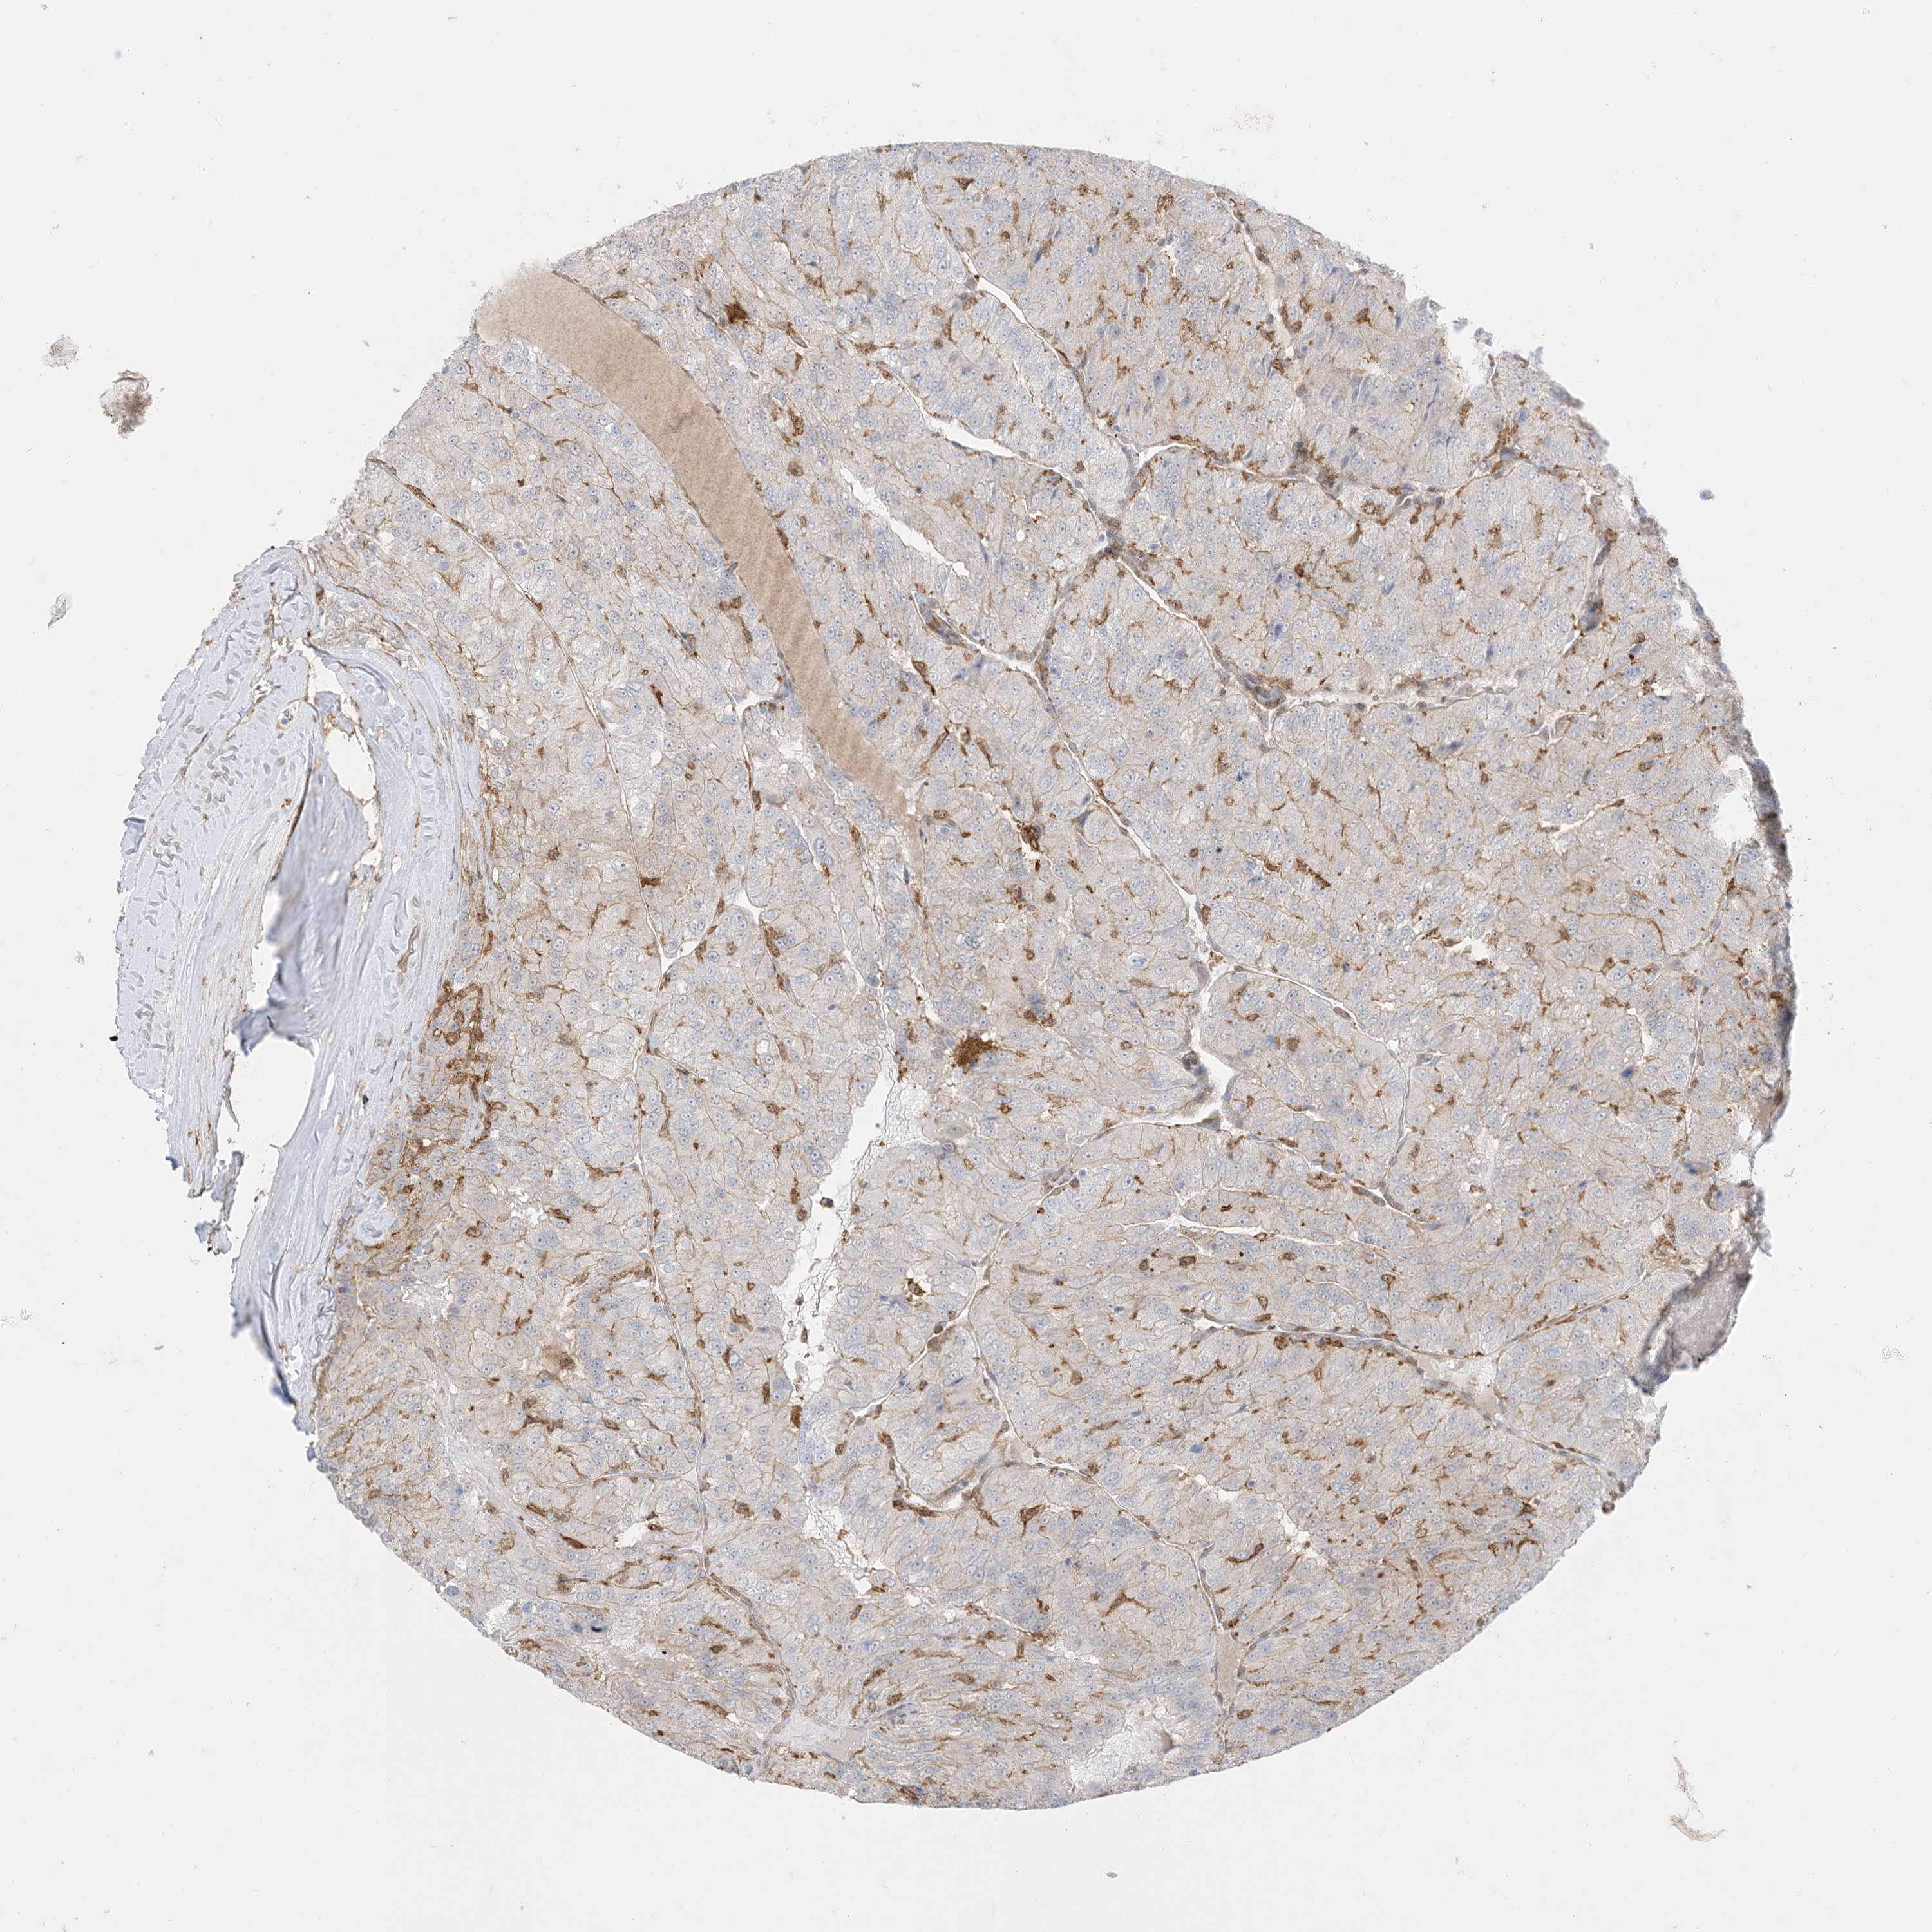

KIDNEY RENAL CLEAR CELL CARCINOMA (VALIDATION) - Interactive survival scatter ploti

The Survival Scatter plot shows the clinical status (i.e. dead or alive) for all individuals in the patient cohort, based on the same data that underlies the corresponding Kaplan-Meier plots. Patients that are alive at last time for follow-up are shown in blue and patients who have died during the study are shown in red.

The x-axis shows the expression levels (FPKM) of the investigated gene in the tumor tissue at the time of diagnosis. The y-axis shows the follow-up time after diagnosis (years). Both axes are complimented with kernel density curves demonstrating the data density over the axes. The top density plot shows the expression levels (FPKM) distribution among dead (red) and alive patients (blue). The right density plot shows the data density of the survived years of dead patients with high and low expression levels respectively, stratified using the cutoff indicated by the vertical dashed line through the Survival Scatter plot. This cutoff is automatically defined based on the FPKM cutoff that minimizes the p-score. The cutoff can be changed by dragging the vertical line or by entering a cutoff value in the square labeled "Current cut-off".

Under the Survival Scatter plot the p-score landscape (black curve; left axis) is shown together with dead median separation (red curve; right axis). Dead median separation is the difference in median mRNA expression between patients who have died with high and low expression, respectively. It is calculated as follows: median FPKM expression of dead patients with high expression - median FPKM expression of dead patients with low expression. This is intended to aid the user in visually exploring custom cutoffs and the associated p-scores and dead median separation.

Individual patient data is displayed and can be filtered by clicking on one or more of the category buttons on the top of the page. Categories describing expression level and patient information include: high, low, alive, dead, female, male and tumor stages. The scale of the x-axis can be toggled between linear and log-scale by clicking on the "x log" button. Mouse-over function shows TCGA ID, patient information and mRNA expression (FPKM) for each patient.

& Survival analysisi

Kaplan-Meier plots summarize results from analysis of correlation between mRNA expression level and patient survival. Patients were divided based on level of expression into one of the two groups "low" (under cut off) or "high" (over cut off). X-axis shows time for survival (years) and y-axis shows the probability of survival, where 1.0 corresponds to 100 percent.

GSN is validated prognostic, high expression is favorable in Kidney Renal Clear Cell Carcinoma (validation)

Best expression cut offi

Based on the FPKM value of each gene, patients were classified into two groups and association between prognosis (survival) and gene expression (FPKM) was examined. The best expression cut-off refers the FPKM value that yields maximal difference with regard to survival between the two groups at the lowest log-rank P-value. Best expression cut-off was selected based on survival analysis .

When clicking on this number, the vertical dashed line indicating cut-off, the interactive survival plot, and the Kaplan-Meier curve will be adjusted to show results based on the best expression cut-off.

: 192.95

P scorei

Log-rank P value for Kaplan-Meier plot showing results from analysis of correlation between mRNA expression level and patient survival.

N/A

5-year survival highi

5-year survival for patients with higher expression than the expression cutoff.

For melanoma and glioma, 3-year survival is shown.

5-year survival lowi

5-year survival for patients with lower expression than the expression cutoff.